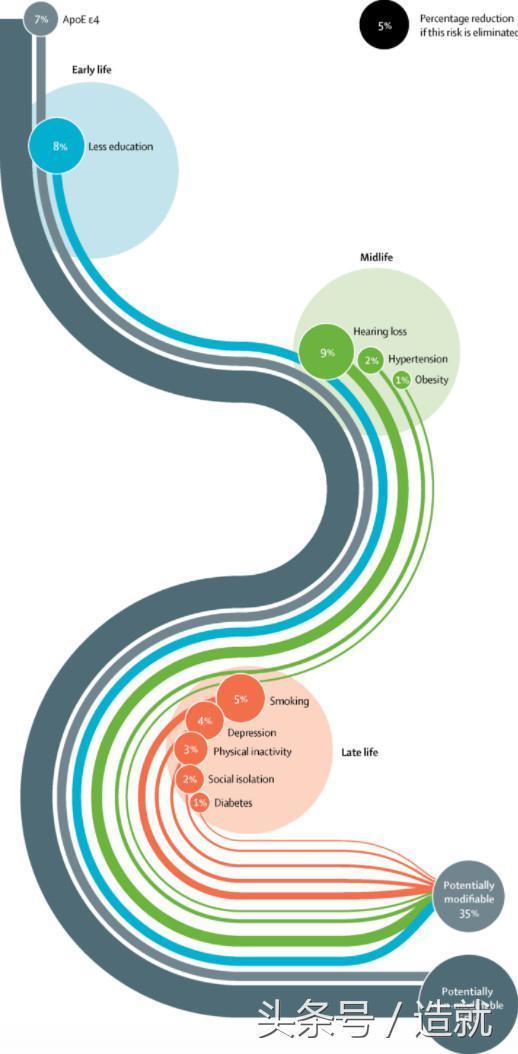

近日,世界各地24位頂尖的癡呆病研究人員在《柳葉刀》上發表論文,列出了生活中9個促成癡呆的因素,它們導致了超過三分之一的癡呆病例。消除這些因素也許能夠使癡呆風險降低35%。

降低癡呆風險的9個方法

癡呆症狀通常在晚年出現,但科學家認為,導致癡呆的大腦變化在早些年就逐漸形成。以下是有助於避免這些變化的9個方法:

而且,並非所有的癡呆病例都可預防:大約7%的癡呆病例與遺傳有關,無法通過生活方式的改變來預防。另外,研究人員寫道:「衰老是最大的癡呆風險因素,但衰老是無法改變的。」